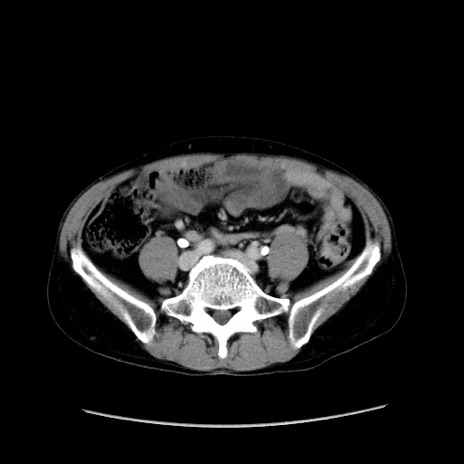

症例37(横断像)

【症例】40歳代 男性

【主訴】腹痛

【現病歴】4時間ほど前に電車に乗車中に臍部上より腹痛出現。徐々に増悪し起立困難となり、救急外来受診。生ものは数日食べていない。今朝お雑煮を食べた。

【身体所見】BT 36.8℃、BP 117/84mmHg、HR 91/min、SpO2 97%、苦悶様、腹部:臍上部広範囲圧痛あり、反跳痛±

【データ】WBC 8100、CRP 0.03